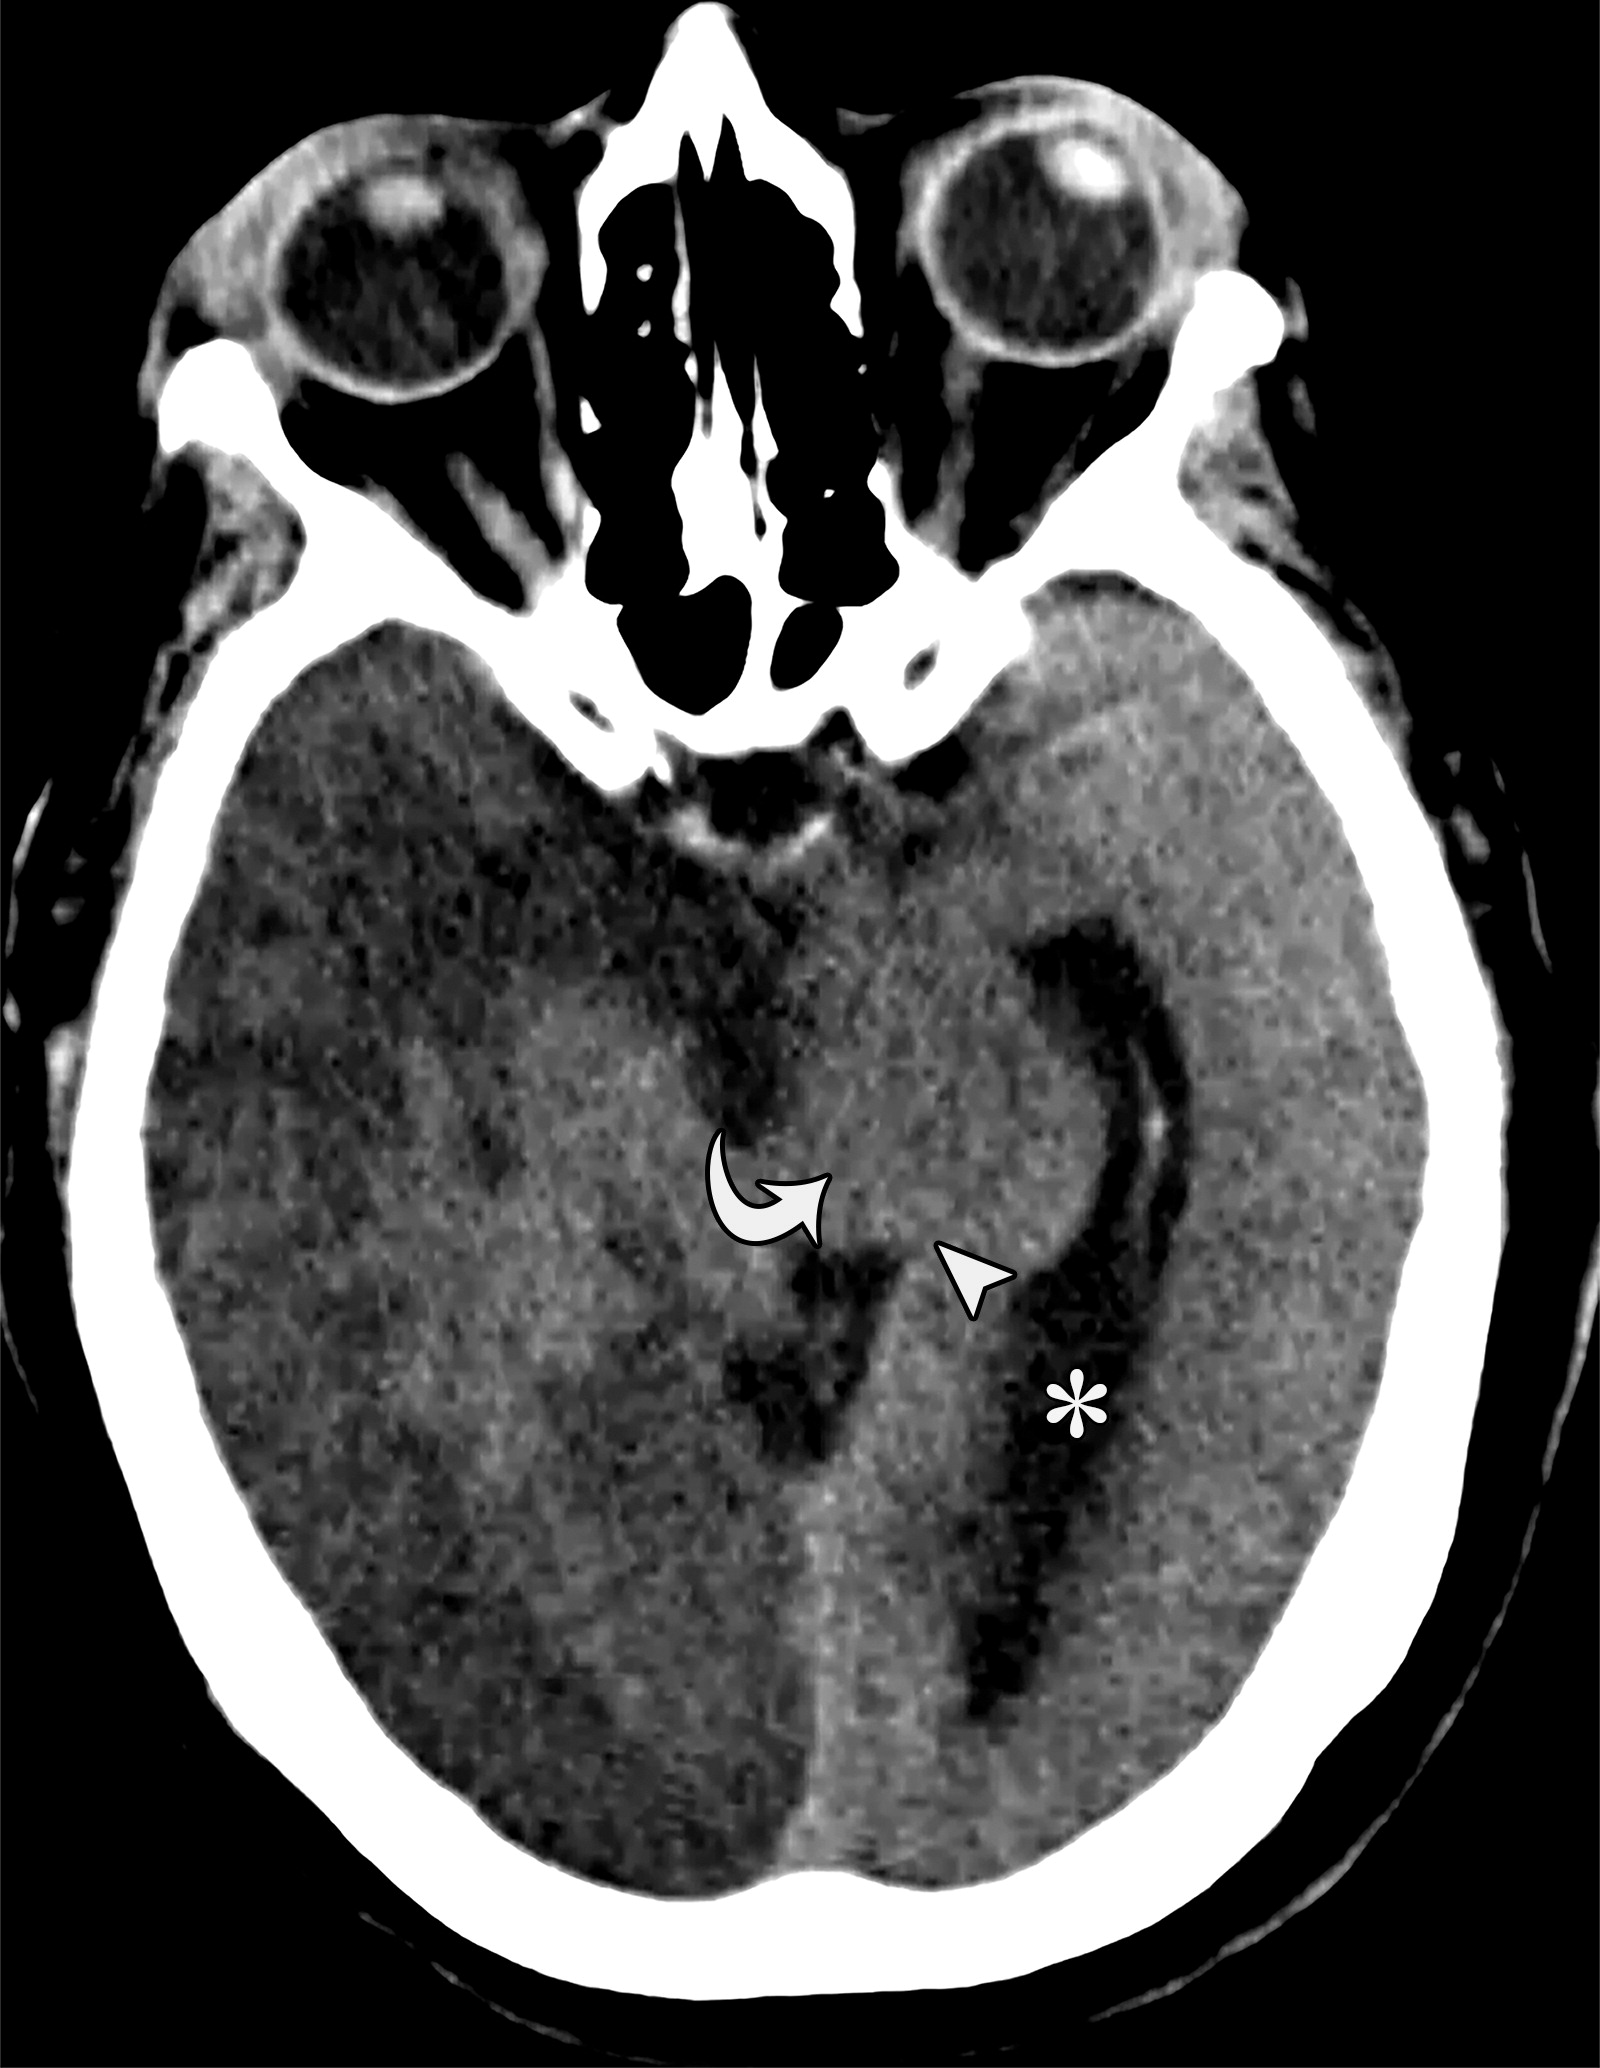

下降性小脑幕裂孔疝。左侧基底池增宽(白色长箭头),右侧基底池消失(白色虚线),右侧侧脑室的颞角扩张(*)。

cb72654f931b7e103fe4a14d193b2b5a.jpeg

下降性小脑幕裂孔疝。中脑受压,旋转,变长(白色短箭头)。中脑周围池完全闭塞。注意对侧侧脑室的增宽(*)。

cbe1ef133c421383c74d5ed9defc43e3.jpeg

26岁男性,终末期肾病血液透析后硬膜下血肿,右侧瞳孔扩张,对光反射消失。钩回向下跨越小脑幕切迹(白色弯曲箭头),同侧的中脑周围池增宽(白色双箭头),对侧中脑周围池受压。注意对侧侧脑室的颞角增宽(*)。